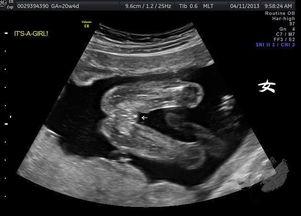

当你第一次看到女宝宝的B超视频时,是不是觉得她就像一个小精灵,在妈妈的子宫里欢快地玩耍?她的眼睛、鼻子、嘴巴,甚至手指脚趾都清晰可见。那一刻,你一定会被这份生命的神奇所感动。

对于很多准妈妈来说,B超视频的最大魅力之一就是可以提前知道宝宝的性别。当你看到那个小小的“X”字时,是不是瞬间觉得整个世界都充满了喜悦?

B超视频不仅能让你看到宝宝的性别,还能帮助你了解宝宝的健康状况。通过观察宝宝的心跳、胎动、羊水等指标,医生可以初步判断宝宝的健康状况。